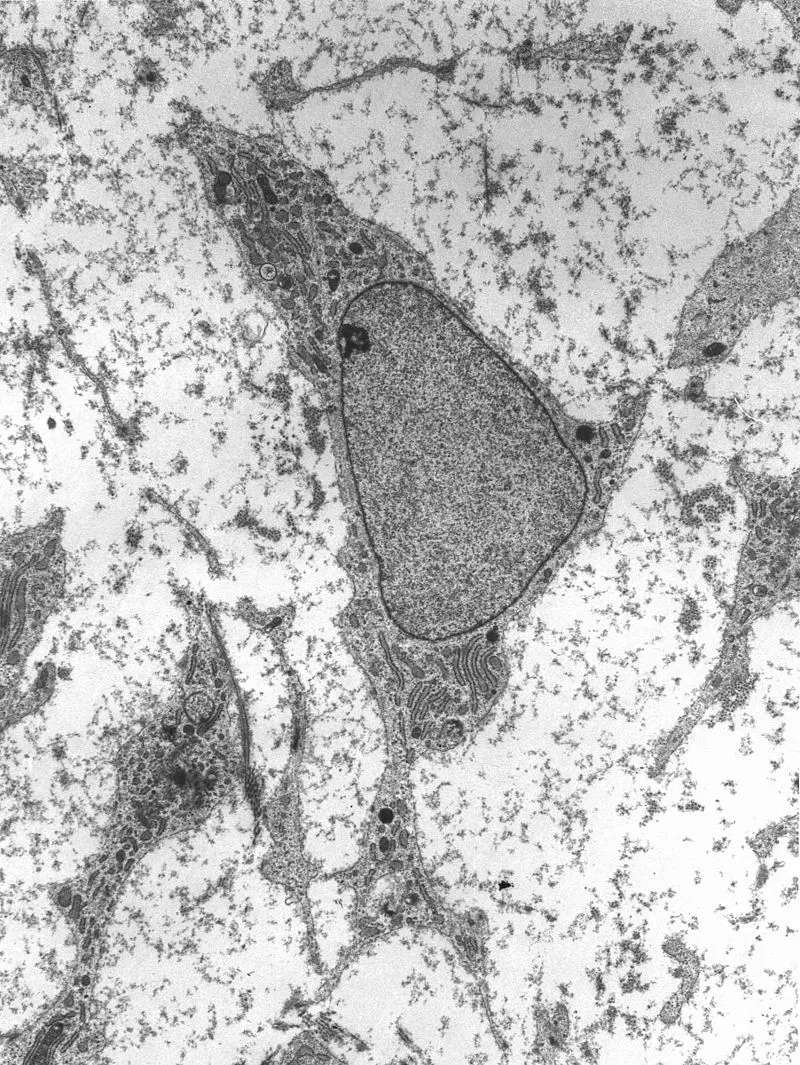

许多研究指出,在组织再生的过程中,干细胞起到了重要的作用。这类细胞经过增殖和分化,发育成具有特定功能的成熟细胞系。根据其分化能力的不同,干细胞又能被分为两类:第一类是多能干细胞(pluripotent stem cells,包括胚胎干细胞和诱导性多能干细胞),第二类是专能干细胞(multipotent stem cells)和单能干细胞(unipotent stem cells,也称成体干细胞)。顾名思义,第二类干细胞的分化能力有限,但它们却在组织再生中扮演了关键角色——组织内的内源干细胞,几乎都是成体干细胞。它们在组织轻微受损后,可协助修复过程,帮助组织恢复正常功能。

专能干细胞的微环境

专能干细胞的微环境能让组织中的干细胞保持长久的自我更新功能,对于它们执行正常的功能有着关键的作用。目前,已经找到了不少案例,涵盖肝脏干细胞、骨髓干细胞、以及种系干细胞、上皮干细胞、神经干细胞等类型。在对这些案例进行分析后,科学家们发现,尽管涉及到细胞种类有所不同,但这些微环境却有许多相似之处。

具体来说,一个典型的干细胞微环境会包括细胞、细胞外基质、以及可溶性因子(如生长因子)。一般而言,这些适合干细胞的微环境深植于组织内部,以维持特定的氧气、离子、生长因子、细胞因子、以及趋化因子的梯度。

科学家们发现,细胞与细胞外基质的相互作用,是干细胞潜力的重要调节与决定因素。不少干细胞位于细胞外基质之中,而后者往往就是干细胞与其子细胞的产物。这些基质由大量分泌蛋白组成,与细胞之间动态互动。人们发现,不同组织或器官的基质有不同的结构特征,往往由其功能所决定。比如对于心脏这一在发育过程中最早获得功能的器官来说,一系列特殊的细胞类型必须在基质中汇集,以配合泵血功能。而在骨骼组织中,基质中的分子则会提供结构上的支持。

而干细胞的分化也会受到基质的影响。基质通过维持其结构的完整性,来维持干细胞的身份,并对它们的激活进行调节。举例来说,细胞外基质刚性的不同,能影响到骨髓干细胞的增殖、迁移、以及分化。此外,除了细胞外基质本身,位于基质中的生长因子和糖蛋白对于干细胞也有重要的调节作用。